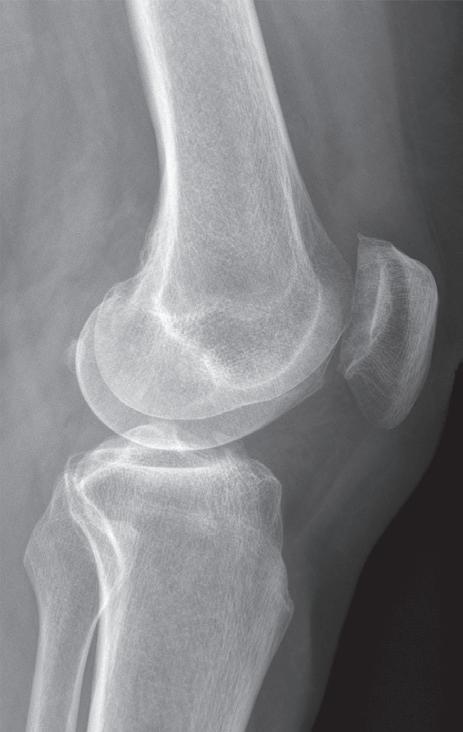

Osteotomie má za cíl korekci kloubní osy se změnou zátěžových oblastí kloubu. Operace obnoví osu končetiny a odlehčí tlak na poškozenou oblast kloubu a zmírní tak subjektivní obtíže nemocného. Příznivý výsledek obvykle přetrvává několik let. Dle poruchy osy rozlišujeme osteomie valgizační (korekce genu varum) a varizační (korekce genu valgum). V praxi se provádí klínovitá osteotomie s vytětím kostního klínu, sesazením obou fragmentů a fixací osteosyntézou (tzv. closed wedge osteotomie, obr. 19.5). Druhou možností je provedení jednoduché osteotomie s rozevřením obou fragmentů v klínovitém tvaru a fixace osteosyntézou (tzv. open wedge osteotomie, obr. 19.6). Dále podle anatomické lokality osteotomie rozlišujeme osteotomie distálního femuru (obr. 19.7) nebo proximální tibie. Artrodéza (ztužení kloubu) se primárně používá ve výjimečných případech (obr. 19.8). Je však možným řešením zejména po selhání aloplastiky, pokud není možná implantace nové náhrady. Vzhledem k faktu, že ztužení kloubu probíhá obvykle v terénu rozsáhlých kostních ztrát, používá se v poslední době ztužení kloubu pomocí implantátů – tzv. fúze kolenního kloubu (obr. 19.9). Nejde tedy v pravém slova smyslu o klasickou artrodézu – tedy kompletní primární kostní srůst femuru a tibie.

Obr. 19.8: Artrodéza kolenního kloubu – patrný srůst resekovaných kloubních ploch femuru a tibie v AP (a) a bočné (b) projekci